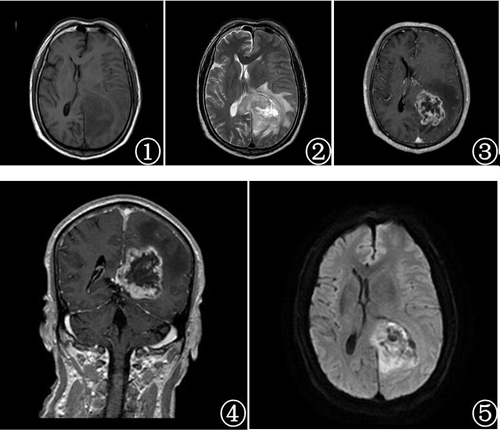

患者老年男性,60岁,因右侧肢体无力1周于2016年2月25入院。患者无明显诱因出现右侧肢体无力,不能上楼,伴右侧偏身麻痹不适,感觉异常,头痛头晕,无呕吐,于当地医院就诊,颅脑CT提示颅内占位。后于本院就诊,实验室检查无明显异常。颅脑MRI检查示左侧颞顶枕叶-胼胝体压部左侧一不规则团块状肿块影,边界较清,大小约为5.5cm×5.4cm×4.9cm,T1WI呈不均匀低信号,T2WI呈不均匀稍高、高信号,液体衰减反转恢复(FLAIR)序列T2WI呈高低混杂信号,其内见多发大小不等囊变区域,增强扫描病灶呈厚壁花环状明显不均匀强化,其内可见多发栅栏样条状强化,周围见较中度水肿带,左侧侧脑室受压变窄。DWI序列显示病灶呈高信号为主,其内间杂多发斑点状低信号。MRS显示病灶内N-乙酰基天门冬氨酸(NAA)峰明显下降,胆碱(Cho)升高,并在1.33ppm处出现高耸的Lip峰。DTI序列显示左侧额枕束中断,病灶周围左侧皮质脊髓、扣带、胼胝体纤维束受推压、移位。术前考虑为恶性肿瘤性病变,考虑胶质母细胞瘤或胶质肉瘤可能。

MR检查能清晰显示胶质肉瘤发生部位、大小、形态、边界、信号及强化特点,以及临近脑实质、脑膜情况。肿瘤为囊实性占位性病变,临近的硬脑膜或大脑镰容易受侵犯。肿瘤边界较清楚,周围伴有不同程度的瘤周水肿,以轻-中度瘤周水肿多见。T1WI肿瘤一般呈低信号,T2WI呈不均匀高信号,注射造影剂后肿瘤表现为均匀或者不均匀强化,边缘强化更加明显,有些表现为厚壁不规则环形强化,特征性强化方式为内部多发栅栏样条状强化。病灶中实性肉瘤成分,由于为非胶质组织中有排列紧密的细胞及纤维基质,在T2WI信号强度较低但增强扫描呈明显强化;而T2WI明显不均匀高信号区域则为伴有囊变坏死的胶质瘤成分。MRS显示病变区域Cho峰升高,NAA峰明显下降,并可以出现代表坏死的Lip峰。DWI显示与大部分恶性肿瘤相似,实性成分表现为高信号,弥散受限,说明肿瘤细胞排列密集。

图1~8患者术前头颅MRI检查。T1WI见左侧颞顶枕叶-胼胝体压部左侧占位,边界清楚肿瘤呈不均匀低信号(图1) T2WI呈不均匀稍高、高信号,其内见囊变区域(图2) 增强扫描病灶呈厚壁花环状明显强化,其内可见多发栅栏样条状强化(图3,4) DWI序列显示病灶呈高信号为主,其内间杂多发斑点状低信号(图5) DTI检查显示左侧额枕束中断(图6),MRS显示病灶内NAA峰明显下降,胆碱峰升高,并在1.33ppm处出现高耸的Lip峰(图7,8)